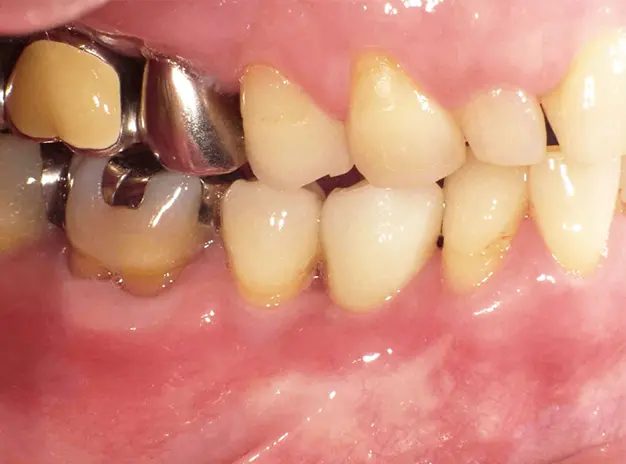

インプラント治療の症例をご紹介

【術前】 【インプラントの光機能化】 【術後】

インプラント治療の症例を紹介します。

下顎の小臼歯が欠損した50歳女性の方は、「自分の歯を極力削らない」「おいしく食事をしたい」「入れ歯の煩わしさから解放されたい」というご希望からインプラントを選択されました。見た目や機能の回復だけでなく、今後の健康維持のために原因への対処や定期的なメンテナンスに取り組まれています。

【治療部位】下顎

【治療期間】4ヶ月間

【治療回数】約10回

【リスク】インプラントが感染することがある

【治療費用】精密検査:16,000円(税込)

一次手術:227,000円(税込)

※手術管理費、仮歯代含む

上部構造:195,000円(税込)

※アバットメント代含む

合計:438,000円(税込)